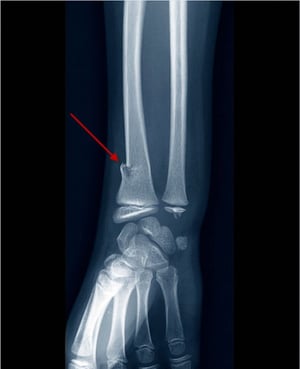

손 통증 손과 손목의 과신전 등쪽 손목의 압통 삼중골 골절

팔꿈치 통증 뻗은 손에 넘어짐 팔뚝을 펴고 발음할 때 팔꿈치 통증 요골 두부 골절

손목 통증 또는 부기 뻗은 손에 넘어짐 해부학적 스너프박스에 대한 압통(반경 바로 원위부에 위치, extensor pollicis longus, extensor pollicis brevis 및 abductor pollicis longus 힘줄 사이) 주상골 골절